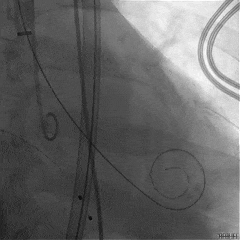

TEER手术过程

建立右侧股静脉入路,在食道超声引导下进行房间隔穿刺,获得穿刺高度4.1cm,交换Super Stiff超硬导丝至左上肺静脉,使用血管鞘扩张股静脉后,沿超硬导丝送入可操控导引导管(SGC)至左房,将第一枚二尖瓣夹输送系统(CDS-XTR)送入左心房。送入夹子过程中为避免碰到左房组织完成Straddle“骑跨”,顺利完成Straddle并将夹子打弯至二尖瓣环水平。接下来为避免发生缠绕在1区进行轨迹测试,使夹子的运动轨迹指向心尖。在心房侧打开夹臂,调整夹臂方向指向12点-6点方位,与二尖瓣对合缘垂直。完成调整后将夹子移动至3区位置,将二尖瓣夹关紧后缓慢送入左心室。在左室打开夹子重新确认Orientation。准确成功捕捞3区前叶脱垂及反流区域,确认瓣叶瓣尖稳定插入夹臂后,Gripper Down,观察到明显Bouncing后,关紧夹臂予以夹合,夹子内侧反流消失,夹子外侧还有残余脱垂及中量反流。考虑瓣叶长度11mm以上,瓣口面积足够,决定在外侧Side by Side再植入一枚XTR,植入两枚XTR后活动稳固,反流降至Trace。术后肺静脉逆流消失,二尖瓣平均跨瓣压差2mmHg。

房间隔穿刺高度4.1cm

SGC穿房间隔进入左房

第一枚XTR进入左房

在1区进行轨迹测试和Orientation调整

将调整好的夹子移动至3区下左室

在左室打开夹子确认Orientation

捕捞瓣叶,确定瓣叶瓣尖稳定插入夹臂后,Gripper Down

Gripper Down后Bouncing明显

夹子关紧后,前后叶受限明显

夹子内侧反流消失

夹子外侧残余脱垂与反流

送入第2枚XTR在左房调整轨迹及Orientation

进入瓣下重新确认Orientation及位置

关紧后,前后叶受限明显

3D Enface下组织桥稳定无反流

夹子释放后,反流基本消失

LVOT切面可见主瓣二尖瓣术后反流基本消失

植入两枚夹子后二尖瓣平均跨瓣压差2mmHg